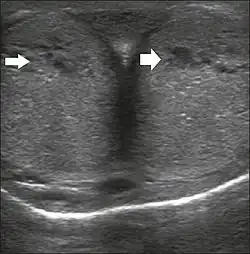

Penile ultrasonography with doppler can be used to examine the erect penis. Most cases of ED of organic causes are related to changes in blood flow in the corpora cavernosa, represented by occlusive artery disease (in which less blood is allowed to enter the penis), most often of atherosclerotic origin, or due to failure of the veno-occlusive mechanism (in which too much blood circulates back out of the penis). Before the Doppler sonogram, the penis should be examined in B mode, in order to identify possible tumors, fibrotic plaques, calcifications, or hematomas, and to evaluate the appearance of the cavernous arteries, which can be tortuous or atheromatous.[48]

Erection can be induced by injecting 10–20 μg of prostaglandin E1, with evaluations of the arterial flow every five minutes for 25–30 min (see image). The use of prostaglandin E1 is contraindicated in patients with predisposition to priapism (e.g., those with sickle cell anemia), anatomical deformity of the penis, or penile implants. Phentolamine (2 mg) is often added. Visual and tactile stimulation produces better results. Some authors recommend the use of sildenafil by mouth to replace the injectable drugs in cases of contraindications, although the efficacy of such medication is controversial.[48]

Before the injection of the chosen drug, the flow pattern is monophasic, with low systolic velocities and an absence of diastolic flow. After injection, systolic and diastolic peak velocities should increase, decreasing progressively with vein occlusion and becoming negative when the penis becomes rigid (see image below). The reference values vary across studies, ranging from > 25 cm/s to > 35 cm/s. Values above 35 cm/s indicate the absence of arterial disease, values below 25 cm/s indicate arterial insufficiency, and values of 25–35 cm/s are indeterminate because they are less specific (see image below). The data obtained should be correlated with the degree of erection observed. If the peak systolic velocities are normal, the final diastolic velocities should be evaluated, those above 5 cm/s being associated with venogenic ED.[48]

Longitudinal, ventral ultrasound of the penis, with pulsed mode and color Doppler. Flow of the cavernous arteries at 5, 15, and 25 min after prostaglandin injection (A, B, and C, respectively). The cavernous artery flow remains below the expected levels (at least 25–35 cm/s), which indicates ED due to arterial insufficiency.[48]